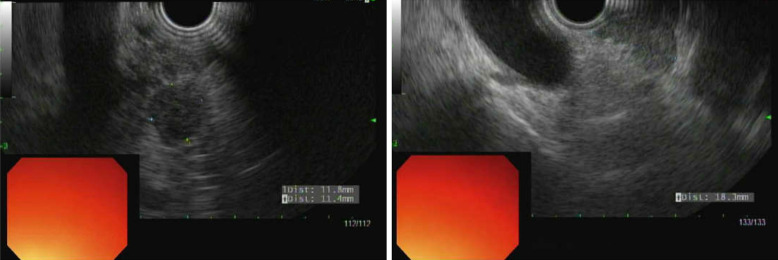

Case presentation: Presented is a 61-year-old male who was found to have synchronous small cell carcinoma and adenocarcinoma of the pancreas confirmed by endoscopic ultrasound-guided fine needle biopsy.